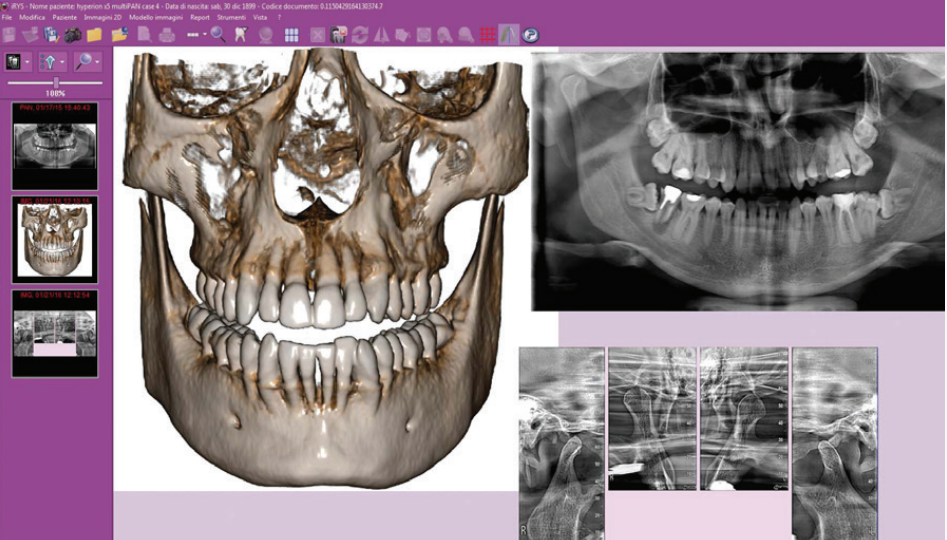

IRYS ile 2D/3D TARAMALARININ YÖNETİMİ 2D ve 3D görüntülerin yönetimi tek bir yazılım üzerinden yürütülür. Çoklu Masaüstü sistemi, 2 boyutlu ve 3 boyutlu görünümler arasında hızlı gezinme mümkündür. Yüksek kaliteli teşhisler yapmak ve hasta ile hızlı bir şekilde iletişim kurmak için ihtiyaç olabilecek her şey IRYS yazılımdadır.

İmplant bölgesini çevreleyen anatomik yapılar hakkında bilgi verir. Kemik kalitesinin değerlendirmesi ve gelişmiş IRYS yazılım özelliğiyle cerrahî prosedürlerin, ameliyat sonrası iyileşme sürelerinin en iyi şekilde planlanması mümkün olur. Bu özellik sayesinde geniş kapsamlı yazılımın implant kütüphanesinde bulunan implantların seçilip konumlandırılarak görüntüler üzerinde planlama yapılabilir.